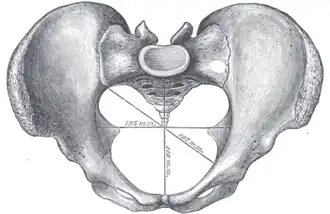

Diameters of pelvic inlet